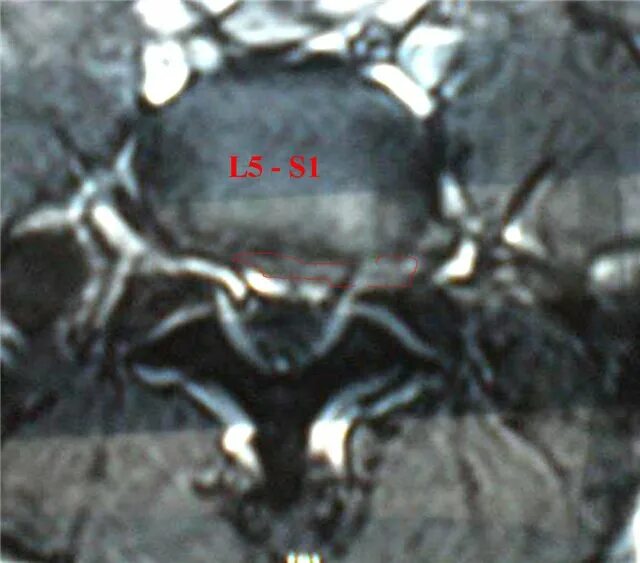

Грыжа экструзия диска l5 s1